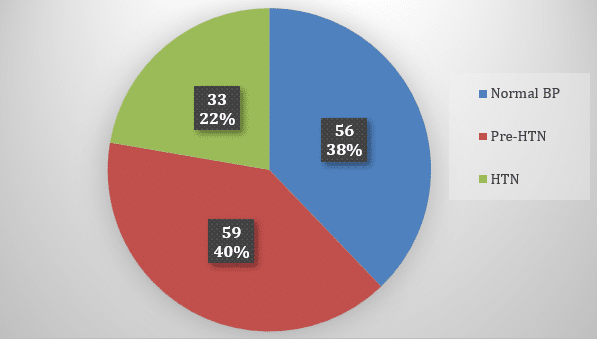

Public Health | May 22, 2025

Scraping the Tip of the Iceberg: Prevalence of Undiagnosed Hypertension Among Patients Presenting to the OPD of Public Tertiary Hospitals, Rawalpindi

Background: Hypertension (HTN), the “silent killer,” is an ever-increasing global health concern, affecting a massive 1.28 billion adults worldwide. Alarmingly,...Read More